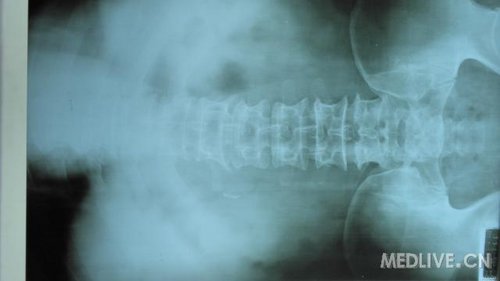

http://webres.medlive.cn/upload/000/030/211

X光片